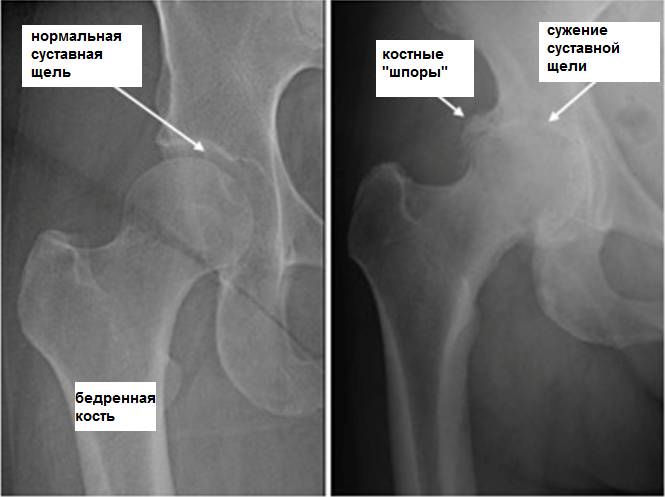

Рентгенологическая диагностика остеоартроза тазобедренных суставов

На точность оценки ширины суставной щели в тазобедренных суставах влияют 3 фактора: позиция больного, поворот конечности и правильная центрация рентгеновского луча при рентгенографии сустава. Сравнение ОА изменений в тазобедренных суставах у одних и тех же больных в 2–х положениях (стоя и лежа) показало, что в положении больного стоя ширина суставной щели была достоверно меньше, чем когда больной лежал на столе. Cуставная щель сужена в большей степени тогда, когда стопа направлена кнутри. Смещение рентгеновской трубки в сторону от центра сустава может достоверно изменить ширину суставной щели. При этом рекомендуется, чтобы центральный рентгеновский луч проходил через центр бедренной головки. Правда, необходимо отметить тот факт, что раздельная рентгенография тазобедренных суставов приводит к увеличению лучевой нагрузки на пациентов.

В начальных стадиях (1–2 стадии по Kellgren) ОА тазобедренных суставов при рентгенологическом исследовании определяются: незначительное сужение суставной щели, слабовыраженный субхондральный остеосклероз, точечные кальцификаты в области наружного края крыши вертлужной впадины (зачаток остеофитов), заострение краев ямки бедренной головки в области прикрепления круглой связки бедренной головки (рис. 1).

Рис. 1. Обзорная Rо-графия тазобедренного сустава в прямой проекции.

Деформирующий остеоартроз II ст. по Kollgren. Крупные остеофиты на краях суставных поверхностей. Грибовидная деформация бедренной головки

В поздних стадиях заболевания (соответствует 3–4 стадии ОА по Kellgren) отмечаются:

• прогрессирующее сужение суставной щели

• формирование различной формы и размеров остеофитов на краях суставных поверхностей вертлужной впадины, бедренной головки, отчего она со временем приобретает грибовидную форму. В средней части вертлужной впадины возможно формирование клиновидного остеофита, который может обусловить латеральное смещение бедренной головки

• углубление вертлужной впадины может быть связано с развитием остеофитов; протрузия ее возможна на фоне остеопороза или истончения костей, составляющих дно вертлужной впадины

• выраженный субхондральный остеосклероз. Проявляется в первую очередь в области крыши вертлужной впадины, затем в верхнем отделе бедренной головки

• в далеко зашедших случаях – уменьшение в объеме и уплощение суставной поверхности бедренной головки на фоне выраженной кистовидной перестройки костной ткани, чередующейся с участками субхондрального остеосклероза. Костные кисты могут быть единичными или множественными. Возникают они в верхней части вертлужной впадины или в зоне наибольшей нагрузки на суставную поверхность бедренной головки

• асептический некроз бедренной головки

• подвывихи бедренной кости чаще вверх и латерально, реже вверх и медиально

• уплотнение костной ткани и укорочение шейки бедренной кости.